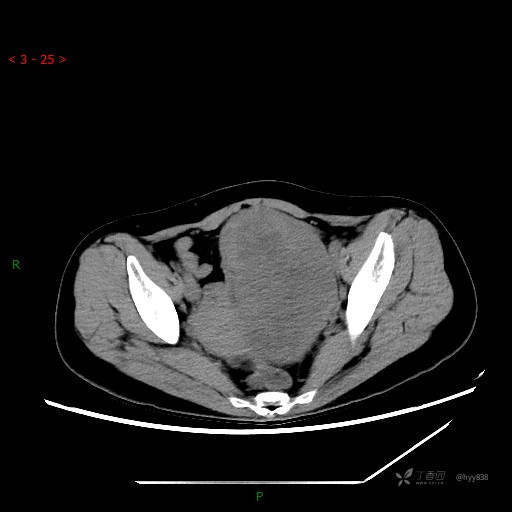

盆腔CT平扫